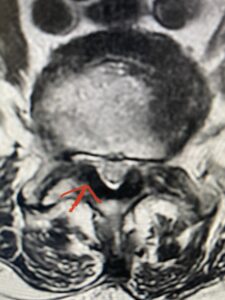

Another patient is a 62 year-old female with progressive low back pain and right leg pain and numbness that radiates to the top of her foot. She tried physical therapy and epidural injections. MRI demonstrated severe L3-4 stenosis and a grade 1 spondylolisthesis (Fig 4). There was L5-S1 and L4-5 disc collapse with modic end-plate changes. Biomechanically because of the significant degeneration of these disc spaces which stiffened the L4-S1 segment more stress was placed on the L3-4 segment, resulting in significant premature degeneration and compensatory stenosis and segmental instability. The MRI also showed pathologically, because of the slip, the L3 inferior processes were more anteriorly oriented and hence contributing to the majority of the lumbar canal compromise. Note the more sagittally-oriented facets in this case compared to the prior case (Fig 5). The patient underwent a decompressive laminectomy with attention of removing the inferior processes of L3 to fully decompress the canal. We also performed an L3-4 fusion with instrumentation (Fig 6). The patient had an uneventful postoperative course with improvement of leg pain. Of note with relief of the disabling leg pain patients are generally very happy. Patients can often manage their low back pain; it is the leg pain that they just can’t tolerate.

Fig 5 Axial T2-weighted lumbar MRI demonstrating significant L3 inferior facet contribution of severe stenosis (blue arrow)